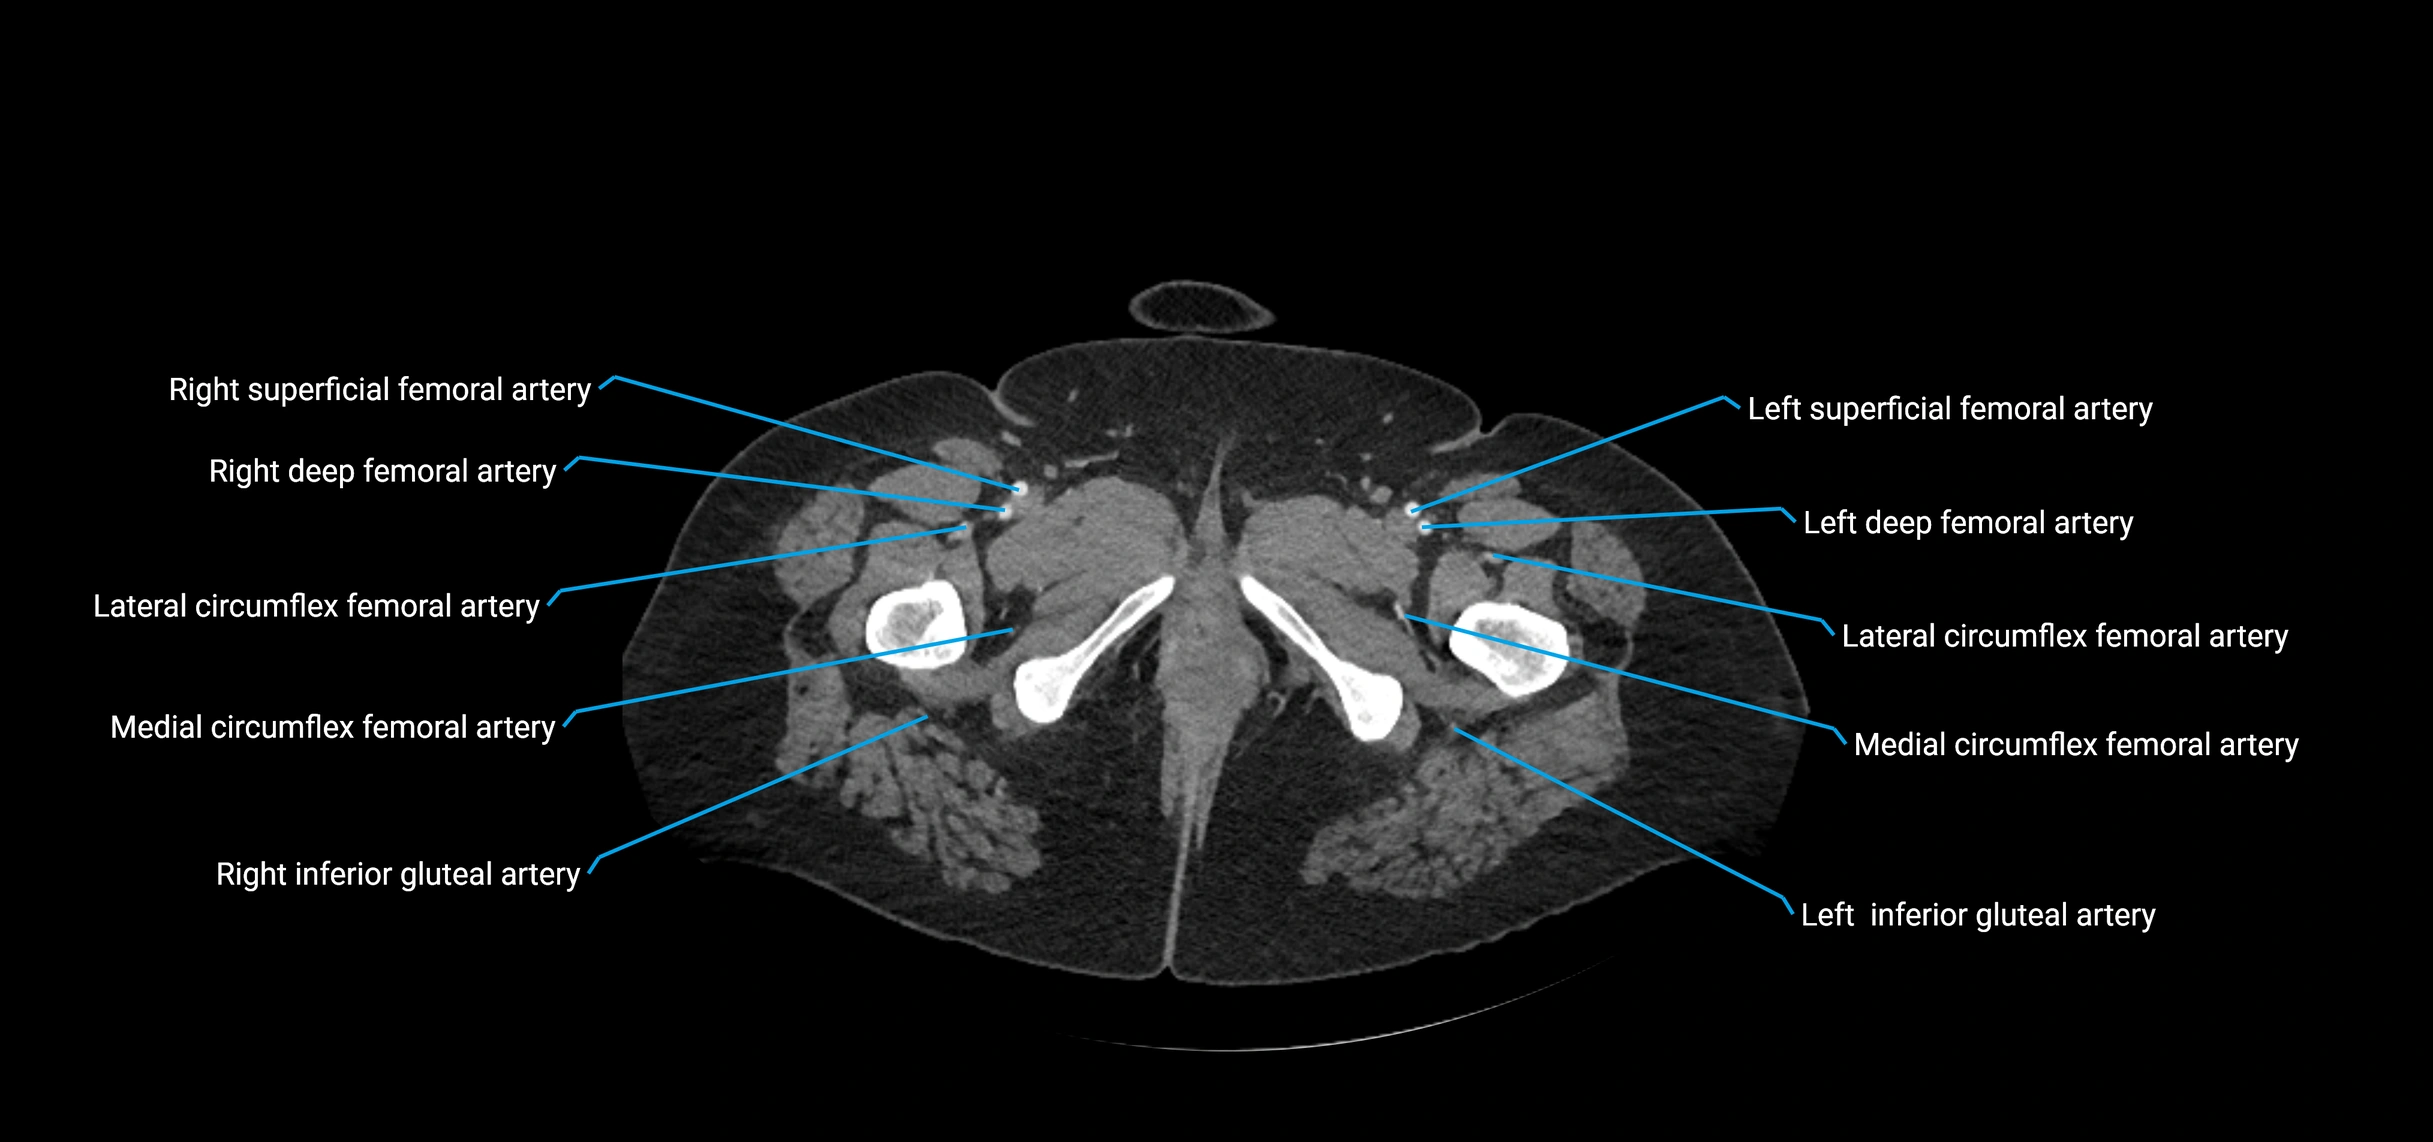

CT Appearance

Non-contrast CT:

• Appears as a tubular soft tissue structure anterior to vertebral bodies

• Calcified atherosclerotic plaques appear as hyperdense foci along the wall

• Useful for screening abdominal aortic aneurysm (AAA) size and mural calcification

Contrast-enhanced CT (CTA):

• Gold standard for abdominal aortic imaging

• Provides excellent detail of lumen, wall, aneurysm, thrombus, and branch vessels

• Multiplanar and 3D reconstructions help in aneurysm measurement, stent graft planning, and dissection evaluation

• Detects acute rupture, traumatic injury, or occlusion with high sensitivity